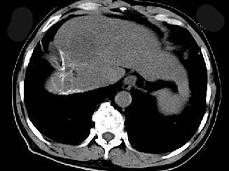

问题 女性,56岁,腹胀、双下肢浮肿、乏力、食欲不振,影像所见如下图,最佳的诊断是 ( )

选项 A.酒精性肝硬化并肝血管瘤 B.血吸虫肝硬化并肝癌 C.肝炎后肝硬化并肝癌 D.局限性脂肪肝 E.原发性肝癌

答案 B